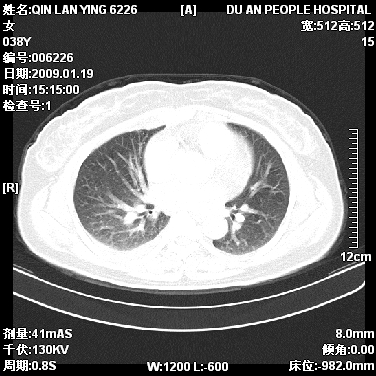

女,38岁,胸疼1个月。wbc:1万4

1)右肺中央型肺癌并右肺上叶阻塞性肺炎、节段性肺不张,纵隔淋巴结转移、右侧胸膜转移、肝脏转移。2)右侧胸腔少量积液。

1、右侧中央型肺癌并阻塞性肺不张,纵隔内、主动脉弓旁、右肺门淋巴结及肝脏转移可能性大,建议纤支镜进一步检查。

本病例有几个容易诊断的地方:1、右肺上叶前段支气管闭塞,肺不张。2、淋巴结明显肿大。3、肝脏多个类圆形低密度影呈“牛眼征”改变,高度提示转移。

从影像学角度分析      右肺上叶中央型肺癌,并阻塞性不张、肺炎,纵隔淋巴结、膈顶淋巴结转移。